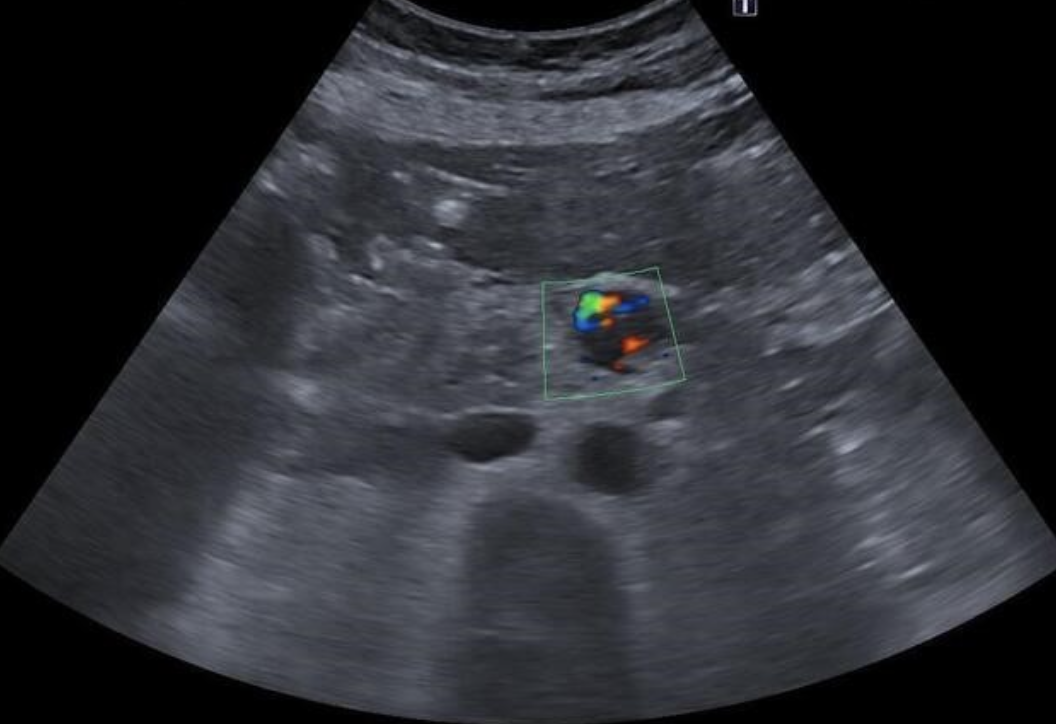

AVF (Arteriovenous Fistula) → abnormal connection between artery and vein in kidney

2D US: cystic space

color doppler: focal aliasing

DDX: aneurysm